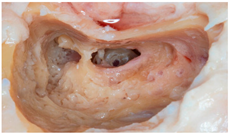

Figure 3. Summary of the sample distribution based on the type of hearing loss, the use of a coupler, and the FMT coupling location. The right column shows the situation both intraoperatively and in imaging tests, as well as representations that exemplify the versatility and different positions the implant can occupy, with or without a coupler, in the middle ear.

Regarding the etiologies of implantation, we found that, as seen in Figure 3, the most frequent audiometric pattern was mixed or conductive hearing loss in a total of 47 patients (85.45%). Among these, the most common cause was cholesteatomatous chronic otitis media (COM) in 20 patients (36.36%), followed by non-cholesteatomatous COM in 10 patients (18.18%), the presence of a retraction pocket in 5 patients (9.09%), and otosclerosis in 4 patients (7.27%). Less frequent causes included post-trauma with ossicular chain damage in three patients (5.45%) and keratosis obturans in two patients (3.64%). Malformations, both of the external and middle ear, accounted for four patients (7.27%), and the least frequent categories, each with one patient (1.82%), were post-radiotherapy necrosis in a patient with a history of nasopharyngeal carcinoma and iatrogenic external auditory canal stenosis.

When studying the gain behavior based on anchorage, we found that out of the total implanted patients, 41 (74.54%) used coupling in the round or oval window, as described in Figure 2. Among these, 24.39% (n = 10) used a coupling system. Of these patients, 39 (95.12%) had conductive or mixed hearing loss, while the remaining two (4.88%) had sensorineural hearing loss.

3.2.2. Ossicular Chain Coupling